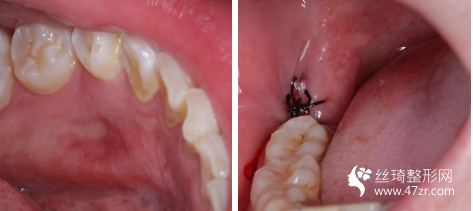

3.武漢葉子醫(yī)療美容醫(yī)院葉飛主治醫(yī)師案例展示

正畸是可以改變臉型,但是不是所有的情況都可以。 一般只有齙牙(只知道這個(gè)情況可能還有別的情況), 或其他比較嚴(yán)重的問(wèn)題通過(guò)正畸才會(huì)有比較明X的臉型變化。 我也是一個(gè)典型想要通過(guò)正畸改變臉型為目的的病例。

一開(kāi)始身邊的朋友都不理解我為什么要整,都覺(jué)得我的牙齒問(wèn)題不大,其實(shí)只有我自己知道,它影響了我的臉型以及我的心理健康。感覺(jué)沒(méi)有這段時(shí)間太大的變化,因?yàn)樽陨淼脑?,我也去不了醫(yī)院了,只能在家候著,牙齒已經(jīng)完全沒(méi)有了感覺(jué),我覺(jué)得應(yīng)該要去加力了,中間有時(shí)候睡覺(jué)的時(shí)候會(huì)壓著牙套,有點(diǎn)感覺(jué),其余時(shí)間是完全沒(méi)有感覺(jué)了,牙齒較后面還是有牽拉感,吃飯的時(shí)候偶爾會(huì)塞牙套,其余的就沒(méi)什么啦